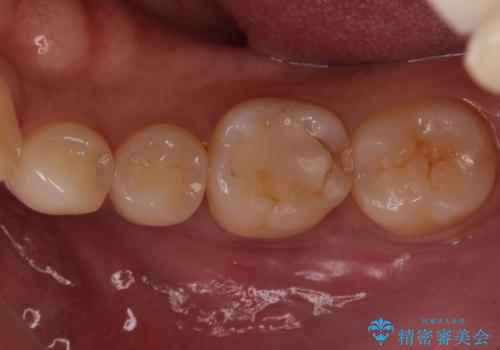

奥歯が欠けた セラミックインレーでの治療

- 奥歯が欠けたとのことで来院されました。

白い詰め物をご希望されたため、セラミックインレーでの治療を行います。

治療前後で比べると、詰め物と歯の間のすき間もなくなりセラミックインレーの適合の良さが伺えます。